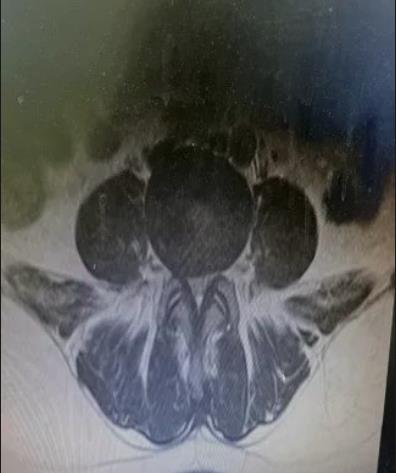

60岁的王某,女性,有3年“腰椎间盘突出伴椎管狭窄”病史。最近,她的腰痛加重,感觉到疼痛向双侧臀部放射,伴有双下肢沉重感。只能走大约300米就需要停下来休息,给她的日常生活带来很大困扰。王某来到市中心医院就诊,与骨科一病区医师详细交流,经仔细检查,发现患者病情比较严重,保守治疗效果不佳,而且狭窄部位比较深,采用普通的单轴椎间孔镜手术可能效果不好。经过骨一科医疗团队共同讨论,决定采用创伤小、恢复快、椎管减压更彻底的微创方案-UBE技术进行治疗。

做好充分准备后,程福宏主任、雷广宇副主任、张波副主任医师和张楠副主任医师等人共同合作,术中采用两个约1cm的切口,通过通道进行操作,对狭窄部位进行减压(ULBD),并摘除了突出的髓核。术后,患者明显感觉到双下肢松弛,可以自如行走,第二天手术后满意出院。

UBE技术,即单侧双通道内镜技术(Unilateral Biportal Endoscopy Technique),通过建立两个通道,一个用于观察,一个用于操作,来实施手术。观察通道采用0度或30度内镜,操作通道使用UBE器械。该技术适用于颈、胸、腰椎的退变性疾病,例如腰椎间盘突出、椎管狭窄、退变性滑脱、腰椎手术翻修、神经根型颈椎病、脊髓型颈椎病等,并可进行镜下融合手术。